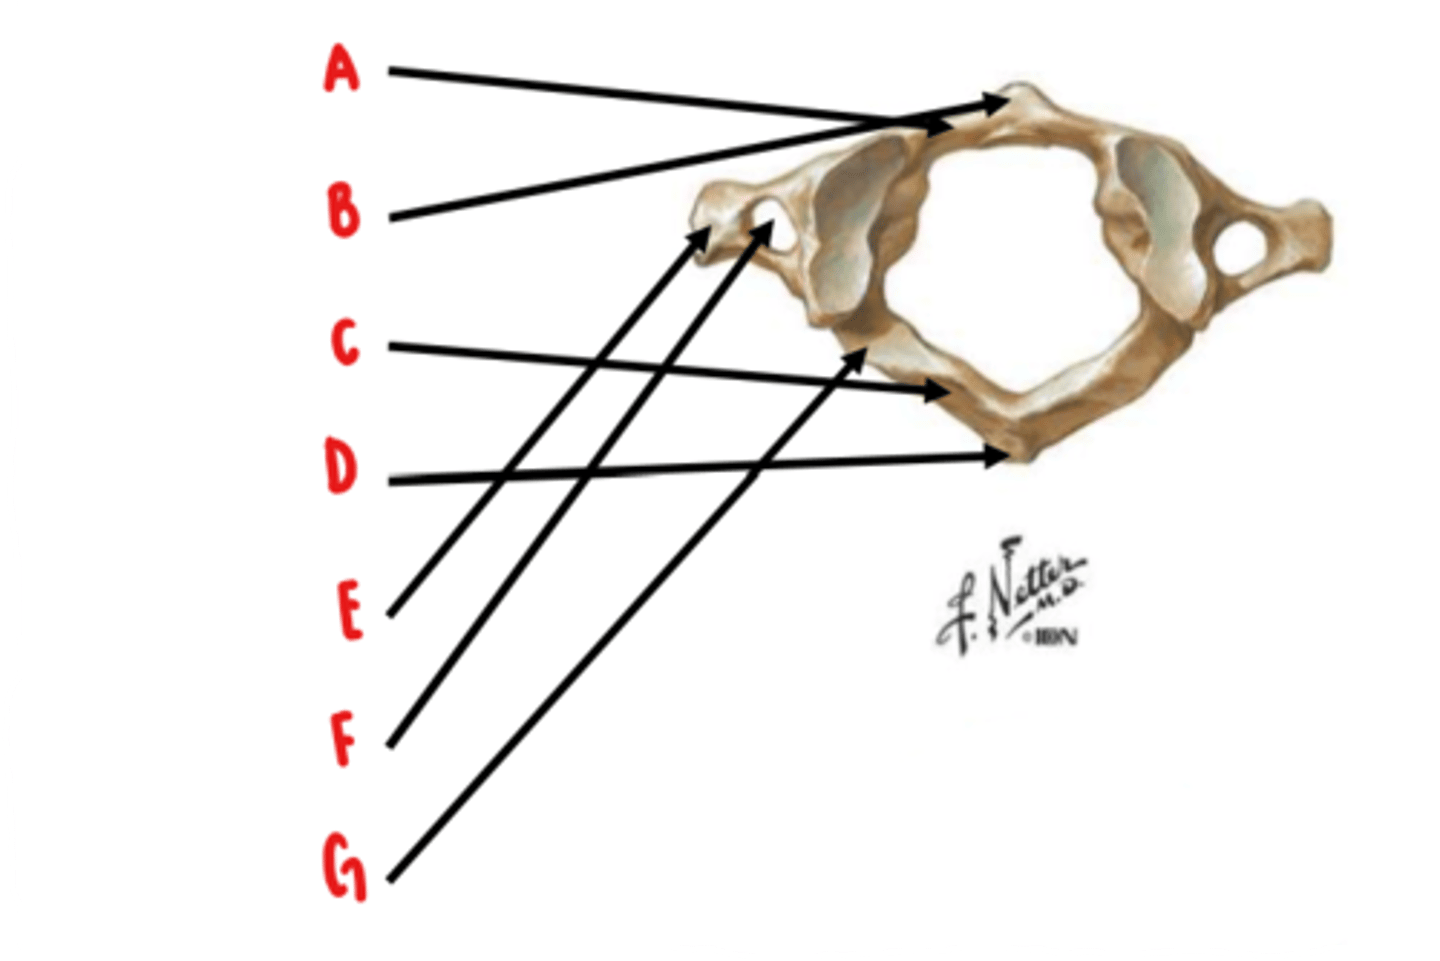

Atlas (C1)

What vertebrae is this?

anterior arch

Identify A

anterior tubercle

Identify B

posterior arch

Identify C

posterior tubercle

Identify D

transverse process

Identify E

transverse foramen

Identify F

groove for vertebral artery

Identify G